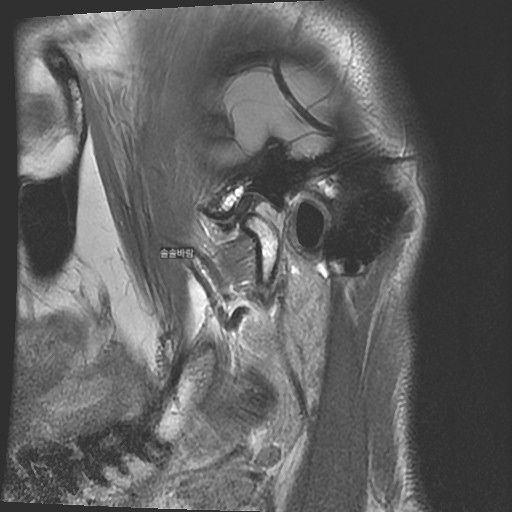

구강내과 턱 MRI 어느 사진이 우측? 좌측?인지 어떻게 보나요? 디스크 두꺼워짐 심한가요?ㅜ

구강내과 턱 MRI 사진 보는데 귀 위치가 다 똑같아서요

어느 사진이 우측? 좌측?인지 어떻게 보나요?

그리고 사진 상 디스크 두꺼워짐 심한가요?ㅜ

현재 사진만으로는 정확히 왼쪽이나 오른쪽이다 라고 할 수 없습니다. 이는 데이터 상의 reference가 필요하며 보통은 해당 부위가 질문자님 기준으로 좌측일 가능성이 가장 크나 이는 좌우 반전을 할 수 있기 때문에 무조건 좌측이라고 할 수 없습니다. 현재 개구시와 폐구시에 보았을 때 condyle (아래턱 부위의 일부)가 disc를 넘어가지 못하고 있으며 이러한 경우 개구제한이 있거나 넘어가더라도 소리가 나면서 넘어갈 수 있습니다. 일부 염증도 보이고 있으므로 내과적인 치료를 하셔야 할 것으로 보입니다.